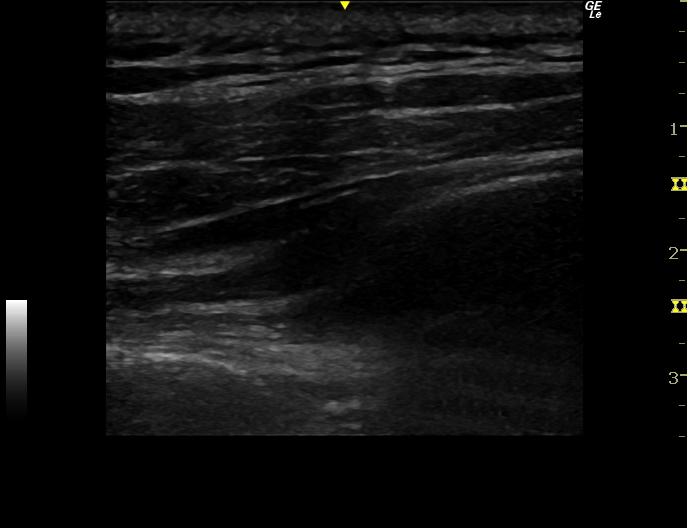

ファシアリリース・筋膜リリース・神経リリース

ファシアリリース・筋膜リリース・神経リリースは神経ブロックとは違いますが、エコーを使用して結合組織、筋膜、神経周辺に生理食塩水などを注入し、痛みやコリを治療するものです。エコーで見ると筋肉の筋膜以外にも、腱や靭帯、脂肪などにも白く厚く重なった癒着した組織が発生します。そこが痛みの原因となったり、組織間の滑走性が低下し可動性が制限されたり、血液の流れが悪くなっている可能性があります。

実際のファシアリリースの動画(再生ボタンを押してください)